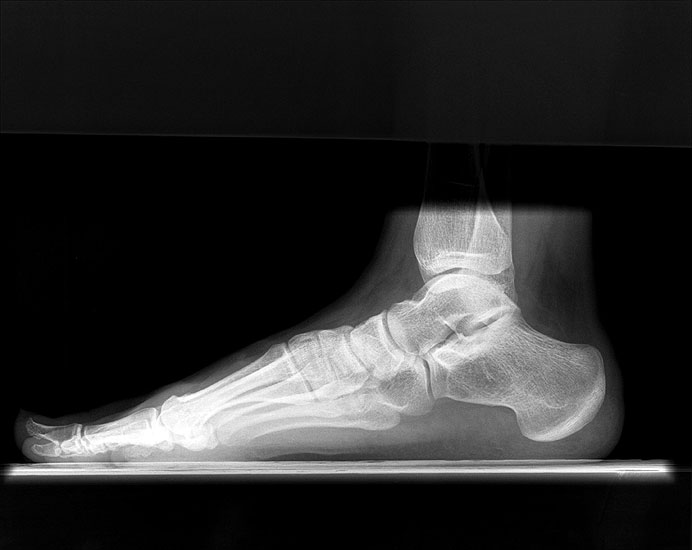

• Röntgenaufnahme des Fußes (unter Belastung) in dorsoplantarem und seitlichen Strahlengang (Abb. 2a-b).

• Beurteilung des proximalen Gelenkflächenwinkels der Grundphalanx (Proximal Phalangeal Articular Angle, PPAA) sowie des distalen Gelenkflächenwinkels der Grundphalanx (Distal Phalangeal Articular Angle, DPAA) 56 (Abb. 3c und 3d).

• Bestimmung des ersten Intermetatarsalwinkels (IMA, Abb. 3a), des Hallux valgus Winkels (HVA, Abb. 3a), des distalen metatarsalen Gelenskflächenwinkels (Distal Metatarsal Articular Angle, DMAA, Abb. 3b) 7. Möglicherweise muss die Akin-Osteotomie mit weiteren Eingriffen kombiniert werden (z.B.: retrokapitale Osteotomie oder andere metatarsale Osteotomie; Arthrodese).